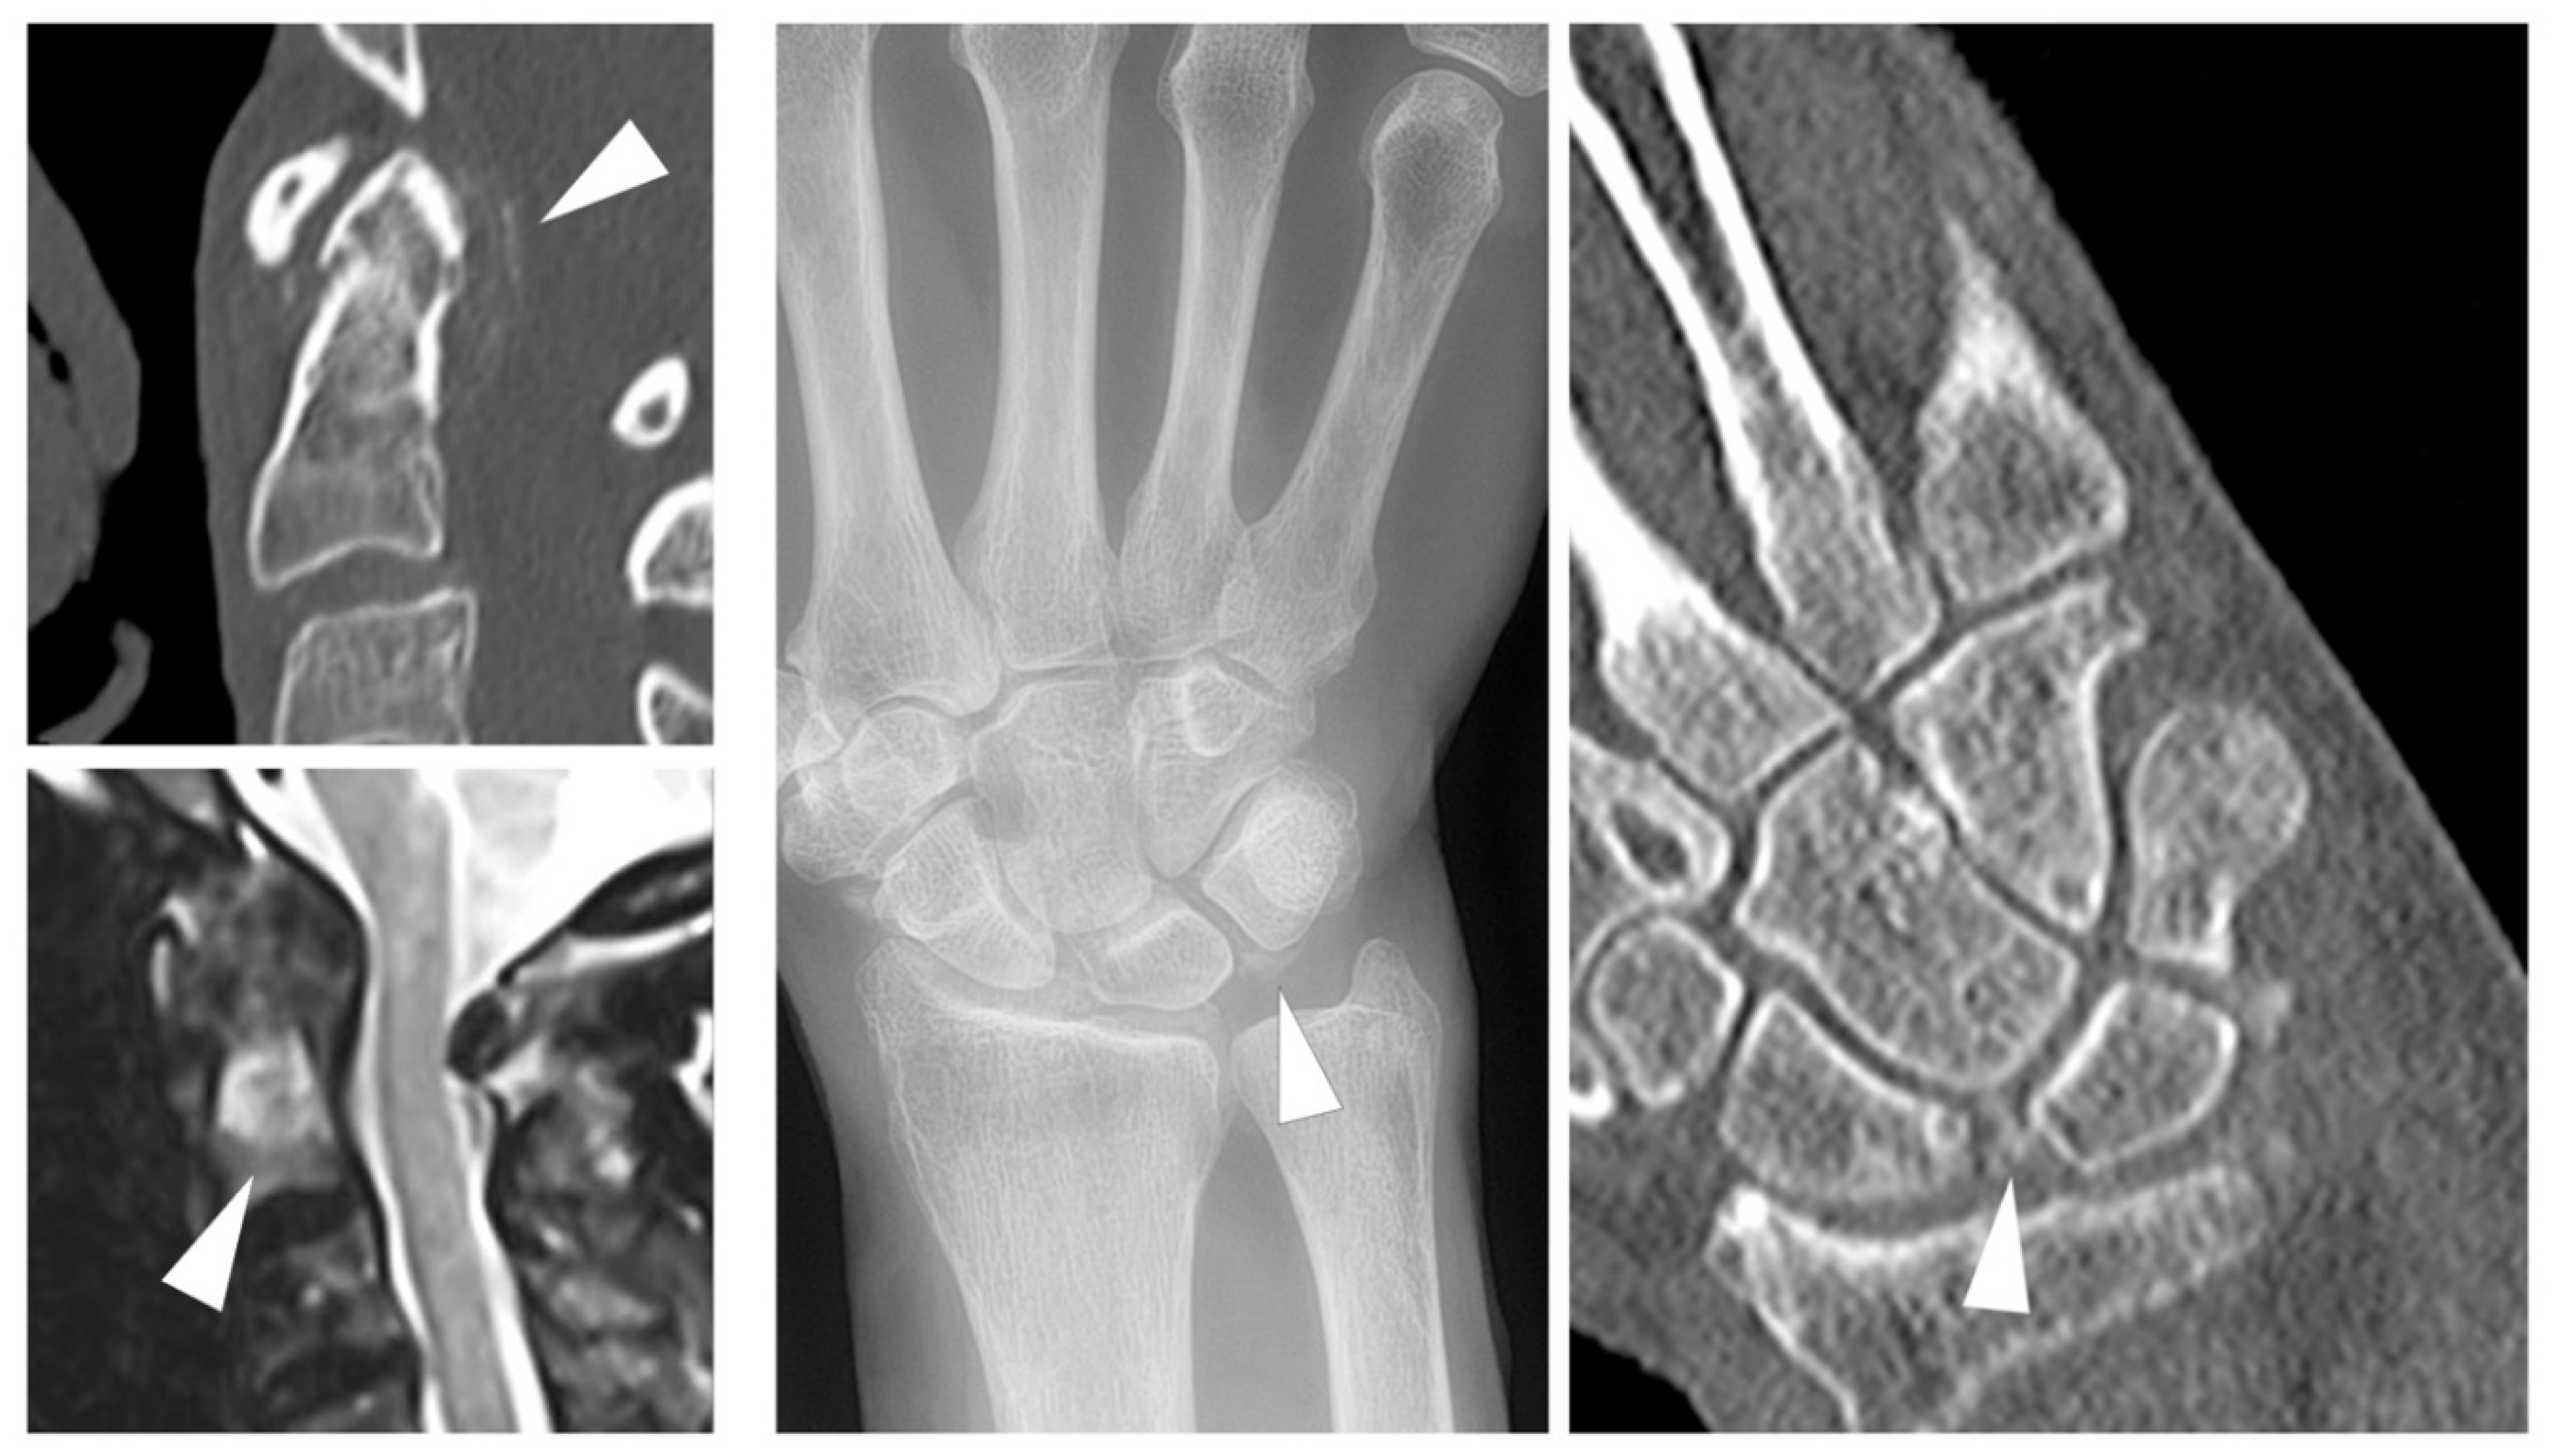

- Chang, E.Y.; Lim, W.Y.; Wolfson, T.; Gamst, A.; Chung, C.B.; Bae, W.C.; Resnick, D.L. Frequency of Atlantoaxial Calcium Pyrophosphate Dihydrate Deposition at CT. Radiology 2013, 269, 519–524. [Google Scholar] [CrossRef] [PubMed]

- Ziegeler, K.; Diekhoff, T.; Hermann, S.; Hamm, B.; Hermann, K.G. Low-dose computed tomography as diagnostic tool in calcium pyrophosphate deposition disease arthropathy: Focus on ligamentous calcifications of the wrist. Clin. Exp. Rheumatol. 2019, 37, 826–833. [Google Scholar]

- Misra, D.; Guermazi, A.; Sieren, J.P.; Lynch, J.A.; Torner, J.C.; Neogi, T.; Felson, D. CT imaging for evaluation of calcium crystal deposition in the knee: Initial experience from the Multicenter Osteoarthritis (MOST) study. Osteoarthr. Cartil. 2015, 23, 244–248. [Google Scholar] [CrossRef]

- Diekhoff, T.; Kiefer, T.; Stroux, A.; Pilhofer, I.; Juran, R.; Mews, J.; Blobel, J.; Tsuyuki, M.; Ackermann, B.; Hamm, B.; et al. Detection and Characterization of Crystal Suspensions Using Single-Source Dual-Energy Computed Tomography. Investig. Radiol. 2015, 50, 255–260. [Google Scholar] [CrossRef]

- Pascart, T.; Norberciak, L.; Legrand, J.; Becce, F.; Budzik, J. Dual-energy computed tomography in calcium pyrophosphate deposition: Initial clinical experience. Osteoarthr. Cartil. 2019, 27, 1309–1314. [Google Scholar] [CrossRef]

- Ziegeler, K.; Hermann, S.; Hermann, K.G.A.; Hamm, B.; Diekhoff, T. Dual-energy CT in the differentiation of crystal depositions of the wrist: Does it have added value? Skelet. Radiol. 2019, 49, 707–713. [Google Scholar] [CrossRef]

- Ziegeler, K.; Richter, S.-T.; Hermann, S.; Hermann, K.G.A.; Hamm, B.; Diekhoff, T. Dual-energy CT collagen density mapping of wrist ligaments reveals tissue remodeling in CPPD patients: First results from a clinical cohort. Skelet. Radiol. 2020, 1–7. [Google Scholar] [CrossRef] [PubMed]

- Moshrif, A.; Laredo, J.D.; Bassiouni, H.; Abdelkareem, M.; Richette, P.; Rigon, M.R.; Bardin, T. Spinal involvement with calcium pyrophosphate deposition disease in an academic rheumatology center: A series of 37 patients. Semin. Arthritis Rheum. 2019, 48, 1113–1126. [Google Scholar] [CrossRef] [PubMed]